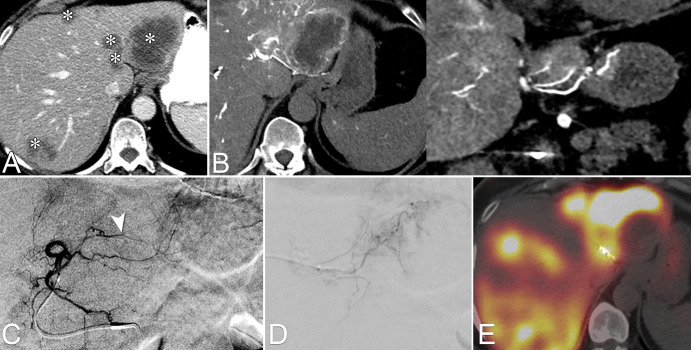

Figure 3:

Extrahepatic tumor supply detected with CT during hepatic arteriography (CTHA) in a patient with multifocal hepatocellular carcinoma. (A) Image from CT during arterial portography shows hypoattenuating tumors in segments 7, 5, and 6 (arrows). (B) Image from CTHA performed from common hepatic artery demonstrates partial tumor enhancement (arrow). (C) Digital subtraction angiography (DSA) image of A7 shows tumor blushes (arrows) and vague enhancement corresponding to S7 tumor (arrowhead). (D) Left: DSA of the right inferior phrenic artery. Middle and right: CTHA and DSA images, respectively, from the distal right inferior phrenic artery demonstrate extrahepatic arterial supply to the S7 tumor arising from the right inferior phrenic artery (arrow and circle). (E) Image from noncontrast CT after conventional transarterial chemoembolization performed via A7 and the right inferior phrenic artery shows adequate lipiodol deposition within the entire extent of the S7 tumor (arrow).

Figure 6:

Images from CT during hepatic arteriography (CTHA) to identify hepaticoenteric collaterals not seen on digital subtraction angiography (DSA) images. (A) Multifocal colorectal liver metastasis to both hepatic lobes (*). (B) Axial and coronal CTHA reconstructions demonstrate an accessory right gastric artery arising from segment II arterial branch. (C) Pre-embolization DSA from the left hepatic artery. On the basis of CTHA images, the arterial branch consisting of the accessory right gastric artery was identified (arrowhead). (D) Selective DSA image depicts the right gastric artery, which was selected and embolized with coils. (E) Image from SPECT-CT with technetium 99m macroaggregated albumin (99mTc-MAA) obtained after embolization of the accessory right gastric artery shows lack of gastric 99mTc-MAA deposition.